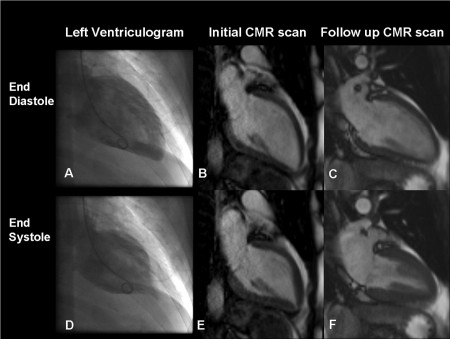

Большинству пациентов обязательно проводят эхокардиографию сердца. Именно на ней в разгар заболевания видны характерные признаки: баллонообразное расширение верхушки, базальная гиперкинезия, акинезия передней стенки межжелудочковой перегородки и значительное сужение выходного отверстия и прилегающих к нему стенок левого желудочка.

По показаниям проводит магниторезонансную томографию, вентрикулографию, коронароангиографию.

Такоцубо – это горшок для ловли осьминога, который используют в Японии. Он имеет округлое основание и горлышко, которое сужается наверху. Именно такую форму принимает сердце, если посмотреть на него с помощью ультразвукового исследования во время развития синдрома Такоцубо.